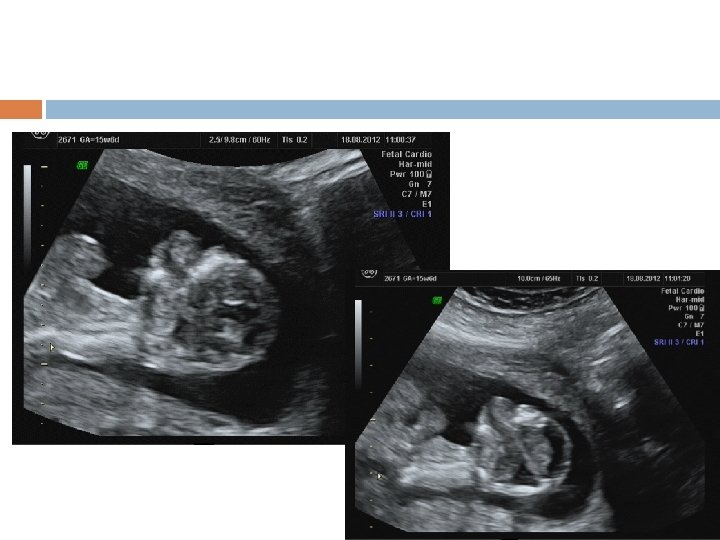

1 ST Trimester Detectable Abnormalities Body stalk anomaly, anencephaly, alobar holoprosencephaly, exomphalos, gastroschisis megacystis. Amelia or Phocomelia

Detectable abnormalities